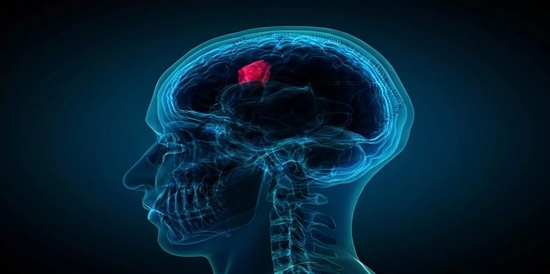

با هدف کاهش خطرات ناشی از جراحی باز مغز و نمونه برداری مستقیم محقق شد؛

ارزیابی نمونه برداری مجازی ضایعات مغزی با استفاده از رادیومیکس و الگوریتم های محاسباتی یادگیری ماشین

پژوهشگران گروه فیزیک پزشکی دانشگاه تربیت مدرس طی پژوهشی به ارزیابی نمونه برداری مجازی ضایعات مغزی با تظاهر رادیولوژیکی مشابه با استفاده از رادیومیکس تصاویر MRI الگوریتم های محاسباتی یادگیری ماشین پرداختند.

روش طلایی تشخیص نوع و درجه تومور برای اعمال روش درمانی موثر انجام نمونه برداری مستقیم از بافت توموری می‌باشد. اما این روش تهاجمی با استفاده از سوزن‌های مخصوص و جراحی باز مغز صورت می‌پذیرد. استفاده از رادیومیکس و الگوریتم‌های محاسباتی یادگیری ماشین بر روی تصاویر MRI می‌تواند در تشخیص افتراقی تومورها نقش به سزایی داشته باشد. دکتر سالار بیجاری که این پژوهش در قالب رساله دکترای تخصصی وی در رشته فیزیک پزشکی انجام شد، با بیان مطلب فوق در خصوص طرح تحقیقاتی خود گفت: در این مطالعه تعداد ۱۹۸ بیمار در ۵ کلاس بیماری جمع آوری و طبقه بندی شدند. . کلاس یک (گلیومای درجه بالا)   48 بیمار، کلاس دو (متاستاز مغزی) ۴۱ بیمار، کلاس سه (مننژیوما مغزی) ۳۸ بیمار، کلاس چهار (آبسه و لنفوم مغزی) ۲۹ بیمار و کلاس پنجم (گلیومای درجه پایین) ۴۲ بیمار که به ترتیب برای هر کلاس ثبت و جمع آوری گردید. ۵ توالی تصویر یابی T1-W، T2-W، T2-W Flair، DWI و T1+CE انجام شد و از هر توالی ۱۰۷ ویژگی کمی با استفاده از نرم افزار‌تری دی اسلایسر و ۹ ویژگی کیفی نیز توسط پزشک استخراج گردید. وی افزود: پس از بررسی ICC ویژگی‌های استخراج شده، ویژگی‌های ICC بالای ۰/۷۵ انتخاب شد. سپس در دو حالت با و بدون تبدیل موجک (۳۰ حالت تبدیل موجک)، ۱۰ روش کاهش بعد و ۱۳ روش یادگیری ماشین بر داده‌های آموزش و آزمون اعمال شد. بیجاری در ادامه تشریح کرد: پس از بهینه سازی مدل‌های مختلف در گروه آموزش، نتایج سطح زیر منحنی راک (AUC)، دقت و F1-score برای گروه آزمون محاسبه گردید. در حالت بدون تبدیل موجک، کاهش بعد PCA و رگرسیون لجستیک بعنوان مدل مناسب انتخاب شد که نتایج AUC،   دقت و F1-score به ترتیب، ۰/۹۴.۰/۹۱ و ۰/۹۰ محاسبه گردید. همچنین در قسمت تبدیل موجک، تبدیل موجک ۵.۵ bior به همراه کاهش بعدلاپلاسین و جنگل تصادفی بعنوان مدل مناسب انتخاب گردید و به ترتیب نتایج آن ۰/۹۷.۰/۹۶ و ۰/۹۶ محاسبه شد. مدل با تبدیل موجک موجب افزایش خروجی مدل گردید. وی در پایان گفت: استفاده از روش‌های رادیومیکس و الگوریتم‌های یادگیری ماشین می‌تواند به تفکیک افتراقی ضایعات مغزی کمک کند و خطرات ناشی از نمونه برداری مستقیم را کاهش دهد. گفتنی است این پژوهش در قالب رساله دکترای تخصصی سالار بیجاری با راهنمایی دکتر پرویز عبدالمالکی عضو هیأت علمی دانشگاه تربیت مدرس انجام شد.